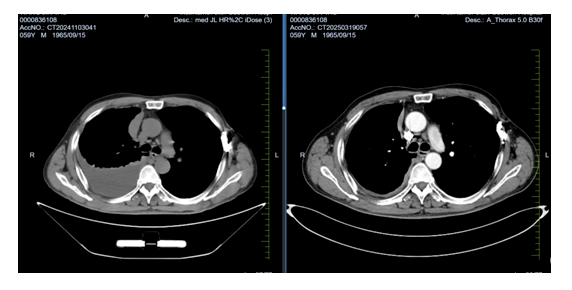

患者家住吉林省白城市鎮(zhèn)賚縣,此次因呼吸困難、胸悶來院就診。入院時患者難以平臥,進食差,體重明顯減輕,胸部腫瘤放化療Ⅱ病區(qū)給予患者行胸部CT檢查,結果顯示:大量胸腔積液,進一步行胸腔穿刺引流并給予完成胸膜活檢,不到一周的時間,病理結果結合免疫組化確診為“惡性胸膜間皮瘤”。這是一種較為罕見的惡性腫瘤,常與石棉暴露相關,預后較差,治療難度大。

經(jīng)過系統(tǒng)治療,患者的胸腔積液明顯減少,呼吸困難顯著改善,日常活動能力恢復,精神狀態(tài)良好。復查影像學顯示腫瘤控制穩(wěn)定,患者及其家屬對治療表示滿意。